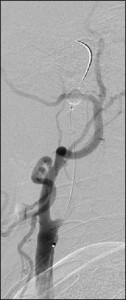

頸動脈ステント留置術(CAS)

![]() 1.ワイヤー通過 |

![]() 2.遠位遮断 |

![]() 3.ステント留置 |

ステント治療前 |

ステント治療後 |